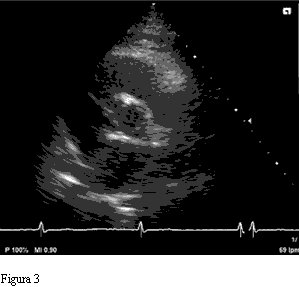

Figura 3 nnnnnnnnnnnnnnnnnnnnnnnnnnnnnnnnnnnnFigura 4

Se presentan las imágenes ecocardiográficas de un hombre de 75 años, tratado por hipertensión arterial, sin síntomas cardiovasculares. El estudio se realizó como rutina para evaluación de su hipertensión.

El ecocardiograma transtorácico mostró un ventrículo izquierdo hipertrófico, con buena función sistólica. La válvula aórtica es cuadricúspide, con cuatro valvas de igual tamaño, y una insuficiencia de grado leve.

Las formas más prevalentes son la tipo B con tres cúspides de igual tamaño y una menor o rudimentaria, y la tipo A, como en nuestro caso, donde las cuatro cúspides presentan el mismo tamaño (8).